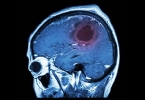

• 大面积脑血栓的治疗方法有哪些

大面积脑血栓的治疗方法有哪些

大面积脑血栓的治疗方法主要有静脉溶栓治疗、血管内介入治疗、抗血小板聚集治疗、抗凝治疗、降颅压治疗等。大面积脑血栓通常由动脉粥样硬化、心源性栓塞、血液高凝状态等因素引起,可能伴随偏瘫、失语、意识障碍等症 ...